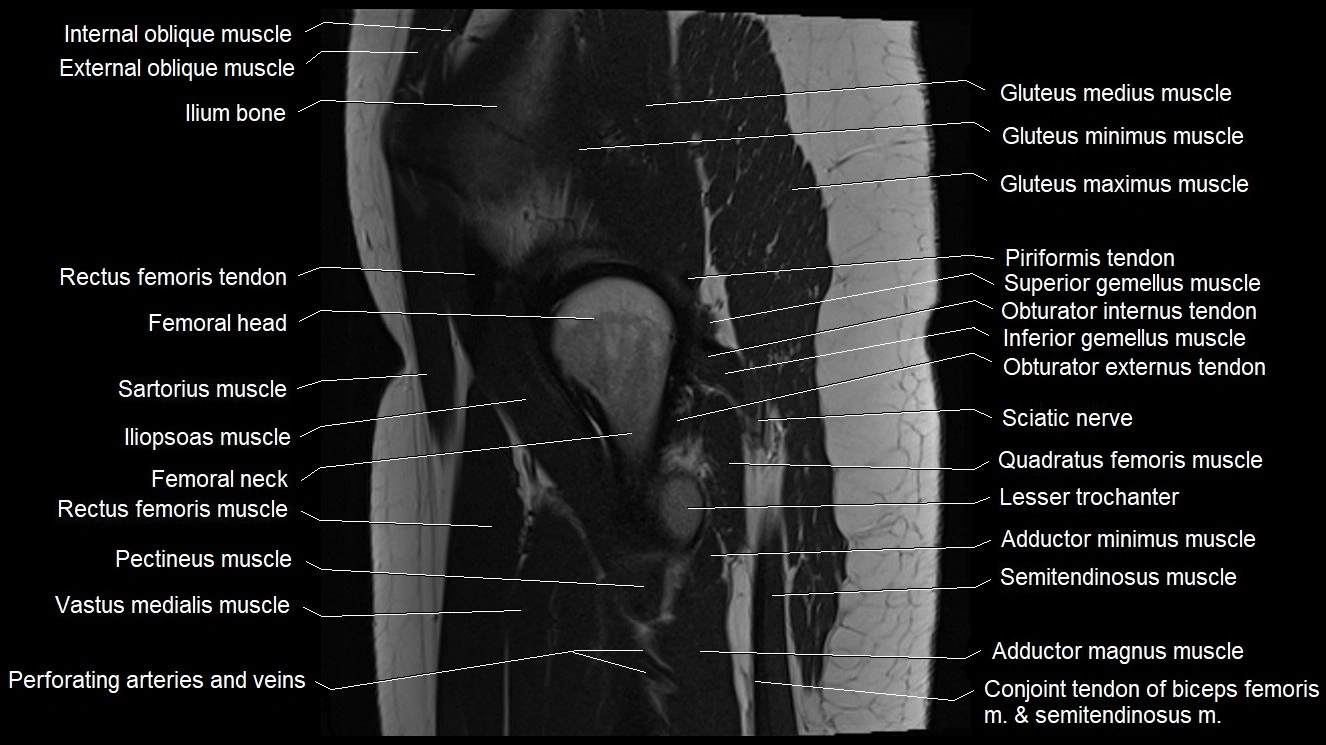

- Ilium bone

- Head of femur

- Neck of femur

- Greater trochanter

- Lesser trochanter

- Gluteus medius muscle

- Gluteus minimus muscle

- Gluteus maximus muscle

- Rectus femoris tendon (Proximal tendon of rectus femoris)

- Rectus femoris muscle

- Sartorius muscle

- Iliopsoas muscle

- Pectineus muscle

- Vastus medialis muscle

- Superior gemellus muscle

- Inferior gemellus muscle

- Obturator internus tendon

- Obturator externus tendon

- Quadratus femoris muscle

- Conjoint tendon of biceps femoris & semitendinosus

- Adductor magnus muscle

- Vastus lateralis muscle